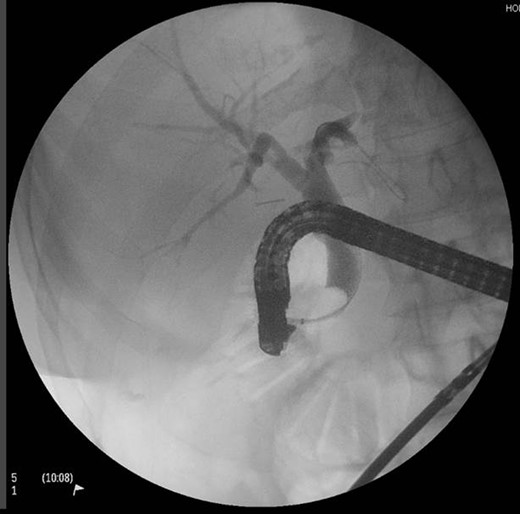

A sterile ERCP scope inserted manually through a left 10-mm port site all under laparoscopic visualization. ERCP and sphincterotomy were performed in the conventional manner by the consultant gastroenterologist. There were no obvious gallstones in our patient (Fig. 2).